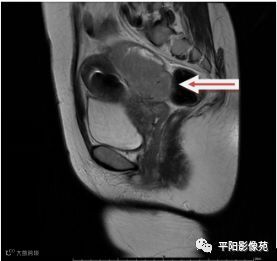

MRI表现

T2矢状位

(宫腔内见金属节育环伪影)宫颈区见不规则形等T1稍长T2信号软组织肿块,DWI序列呈明显高信号,大小约为3.87cmX2.64cm,双侧宫颈基质低信号环连续性中断,病灶向子宫右后上方生长,周围脂肪间隙模糊,增强扫描明显强化,强化程度低于子宫及宫颈实质;子宫后方、子宫直肠间隙见不规则形长T1长T2信号软组织肿块,DWI序列呈高信号,大小约10.12cmX4.82cmX10.29cm,病灶呈分叶状,向下方生长与宫颈分界不清,与直肠分界尚清,增强扫描明显不均匀强化。